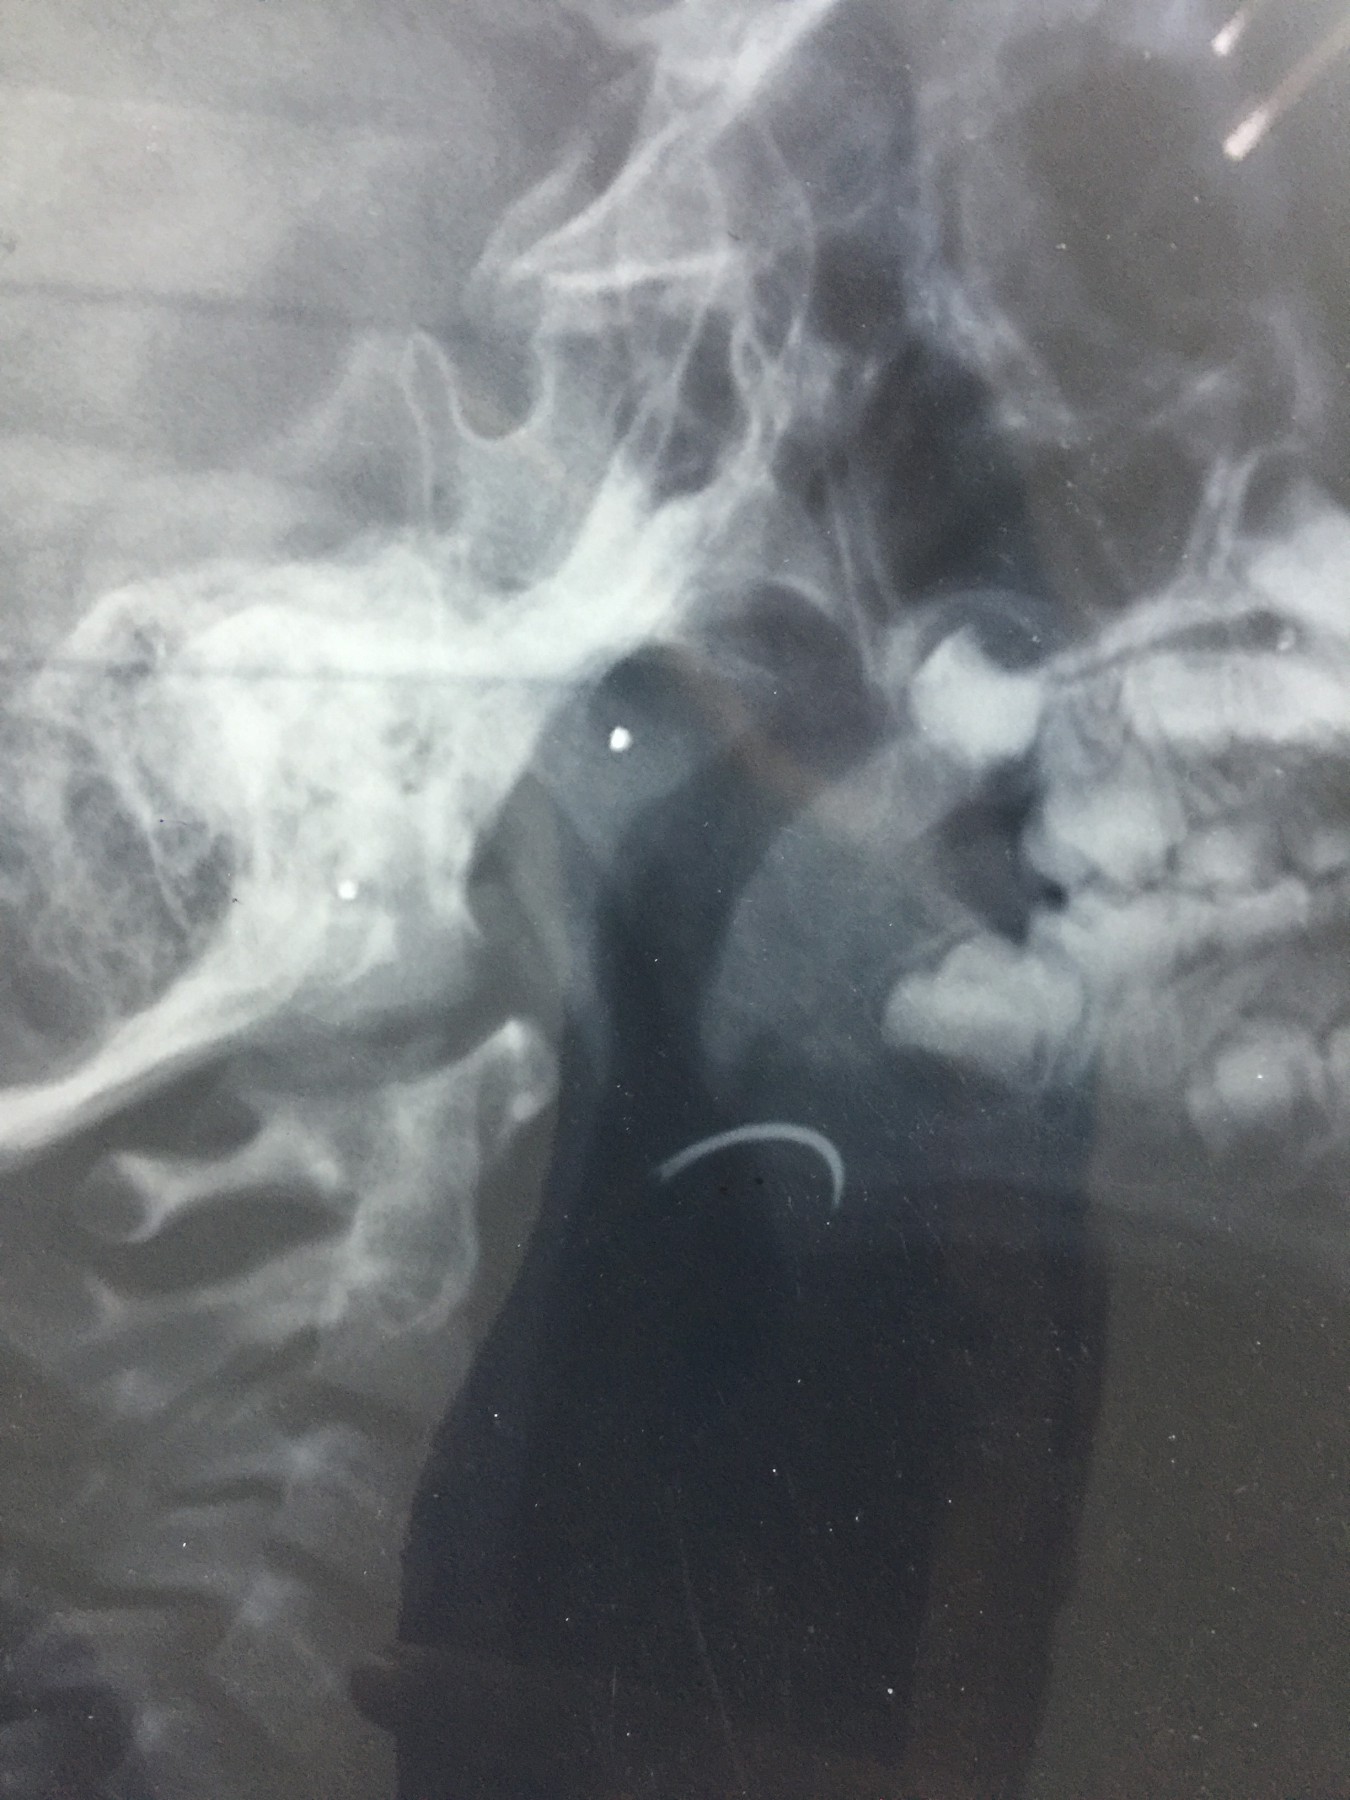

شهد مسلسل الإهمال الطبى حلقة جديدة بمستشفى جامعة طنطا، حيث نسى أحد الأطباء إبرة الخياطة الخاصة بالجروح داخل حنجرة أحد الأطفال خلال إجراء علمية جراحية لإزالة اللوزتين.

وأكد والد الطفل، أن الطبيب اكتشف أنه نسي الإبرة داخل زور نجله، وقام بتخدير نجله مرة ثانية لإخراج الإبرة ولكن دون فائدة، مؤكدا أن الطبيب أكد انه لن يستطيع استخراج الإبرة من الطفل.

وأكد، أنه توجه للدكتور أمجد عبد الرؤوف عميد كلية الطب، والدكتور هشام توفيق المشرف العام على المستشفيات الجامعية للتدخل لإنقاذ نجله، مشيرا إلى أنه تقدم بشكوى ضد الطبيب الذي أجرى العملية “أ.س” لرئيس قسم الأنف والأذن بالمستشفى، وعميد كلية الطب والمشرف العام على المستشفيات الجامعية، مؤكدا أن رئيس قسم الأنف والأذن والحنجرة، استدعى أطباء من خارج المستشفى لإنقاذ نجله، وأكدوا أن فى ذلك خطورة على حياته.